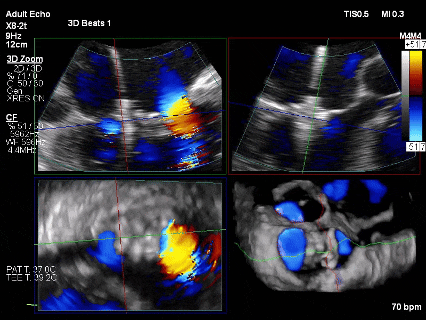

术前3Dcolor

彩色多普勒显示反流明显减少

捕获后反流降至轻度

最终结果3D-Zoom-color显示组织桥稳定,原脱垂区域前后叶对合部分的脱垂已消除,反流降至1+以下

夹子释放Bi-com切面显示残余反流情况

肺静脉收缩期逆流消失,频谱形态基本恢复正常